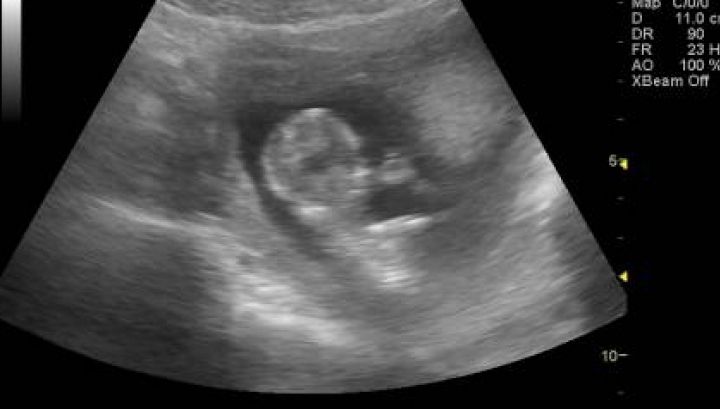

6 feb. 2016, 11:34ActualA rămas însărcinată, dar nu a făcut nicio ecografie. Când a ajuns la spital, medicii s-au îngrozit